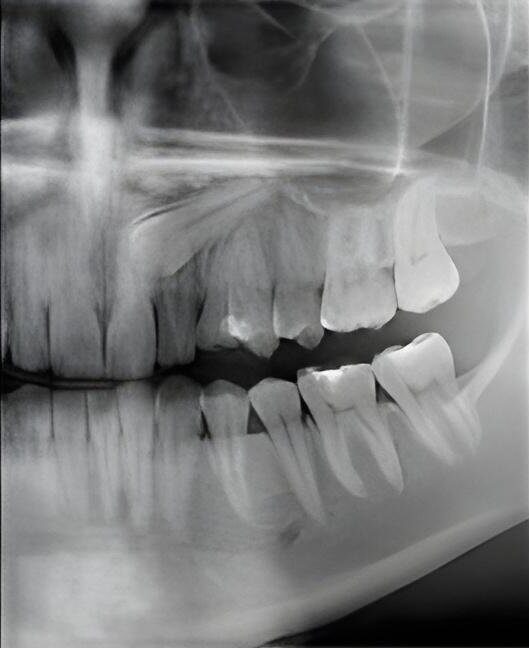

Badania RTG (radiowizjografia cyfrowa):

Zdjęcie rentgenowskie zębów, pokazujące stan jamy ustnej, wykorzystywane w gabinecie stomatologicznym do diagnostyki. Warto skonsultować się z dentystą w celu oceny zdrowia zębów.

Zdjęcia punktowe (intraoralne): RTG pojedynczego zęba, RTG dwóch sąsiednich zębów, RTG w technice skrzydełkowej (bite-wing) do oceny próchnicy międzyzębowej, RTG przywierzchołkowe do oceny stanu korzeni i tkanek okołowierzchołkowych

Zdjęcia okluzyjne: RTG żuchwy w projekcji okluzyjnej, RTG szczęki w projekcji okluzyjnej

Kontrola leczenia: RTG kontrolne po leczeniu kanałowym, RTG kontrolne w trakcie leczenia kanałowego (pomiar długości kanału), RTG kontrolne po ekstrakcji zęba